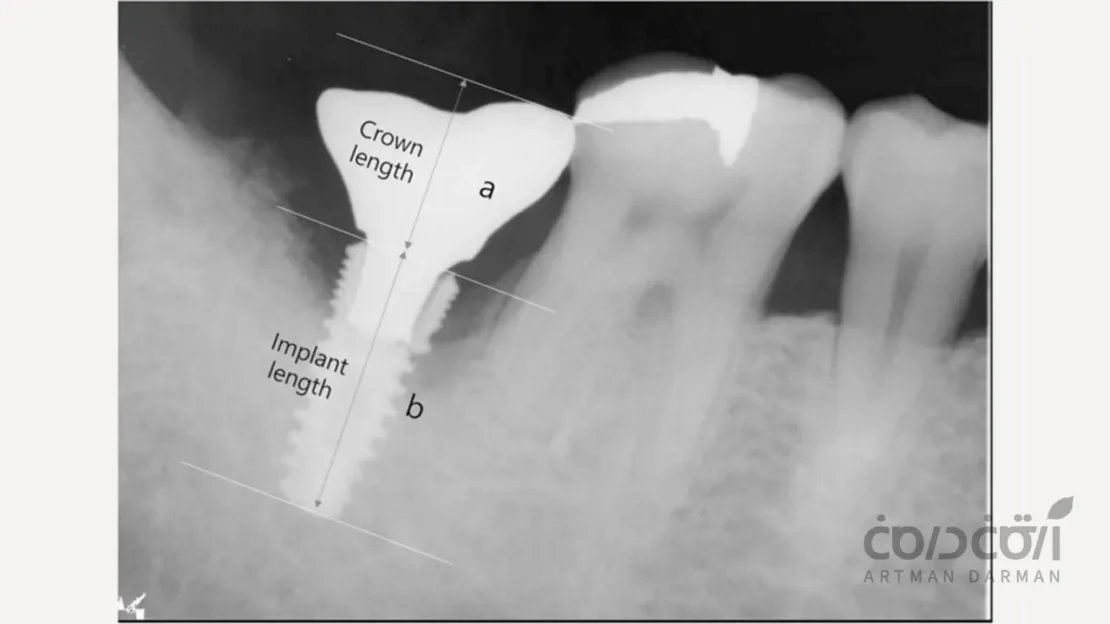

انتخاب قطر نامناسب ایمپلنت

این مورد تقریبا یک اشتباه رایج در طرح درمان است. استحکام یک ایمپلنت رابطه مستقیمی با قطر آن دارد. استفاده از یک ایمپلنت با قطر کم (مثلاً ۳.۵ میلی متر) برای جایگزینی یک دندان آسیاب بزرگ (مولر) که نیروهای جویدن سنگینی را تحمل می کند، مانند قرار دادن یک ستون نازک زیر یک سقف سنگین است. این انتخاب نادرست، ایمپلنت را مستعد شکستگی ایمپلنت دندان می کند.

کاشت ایمپلنت با زاویه نامناسب هم می تواند باعث شکستگی آن در آینده شود. در واقع ایمپلنت ها برای تحمل نیروهای عمودی (در راستای محور طولی خود) طراحی شده اند. اگر یک ایمپلنت با زاویه زیاد کاشته شود، نیروهای جویدن به صورت خمشی و برشی به آن وارد می شوند. این نیروهای غیرمحوری، استرس را در ناحیه گردن ایمپلنت متمرکز کرده و ریسک شکستگی ایمپلنت دندان را افزایش می دهند.